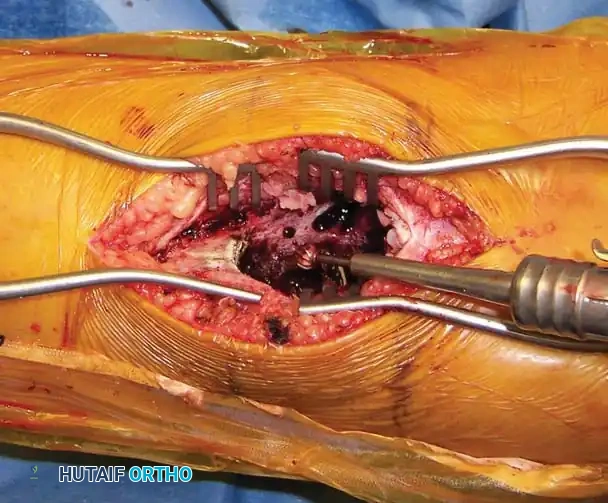

- Gross Curettage: The blood-filled contents and fibrous septations are aggressively evacuated using large curettes.

Intraoperative photograph revealing the multiloculated, blood-filled cavity characteristic of an ABC.

- High-Speed Burr (Extended Curettage): Standard curettage alone leaves microscopic reactive tissue in the bony interstices, leading to high recurrence rates. A high-speed power burr is systematically used to remove an additional 1-2 mm of bone from the entire cavity wall, extending the margin into normal-appearing cancellous bone.